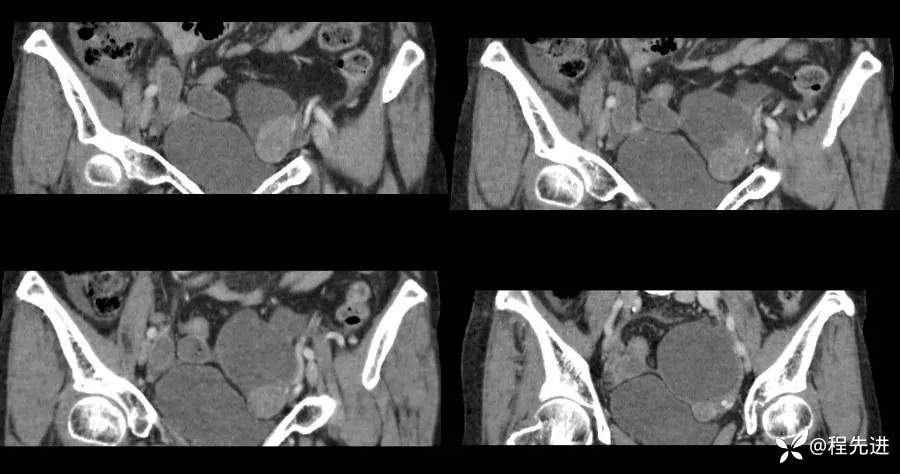

【患者信息】:女,59岁

【主诉】:下腹部不适2月,B超发现盆腔囊性包块。

实验室检查:CA125:239.1u/ml,CA72-4:99.64u/ml